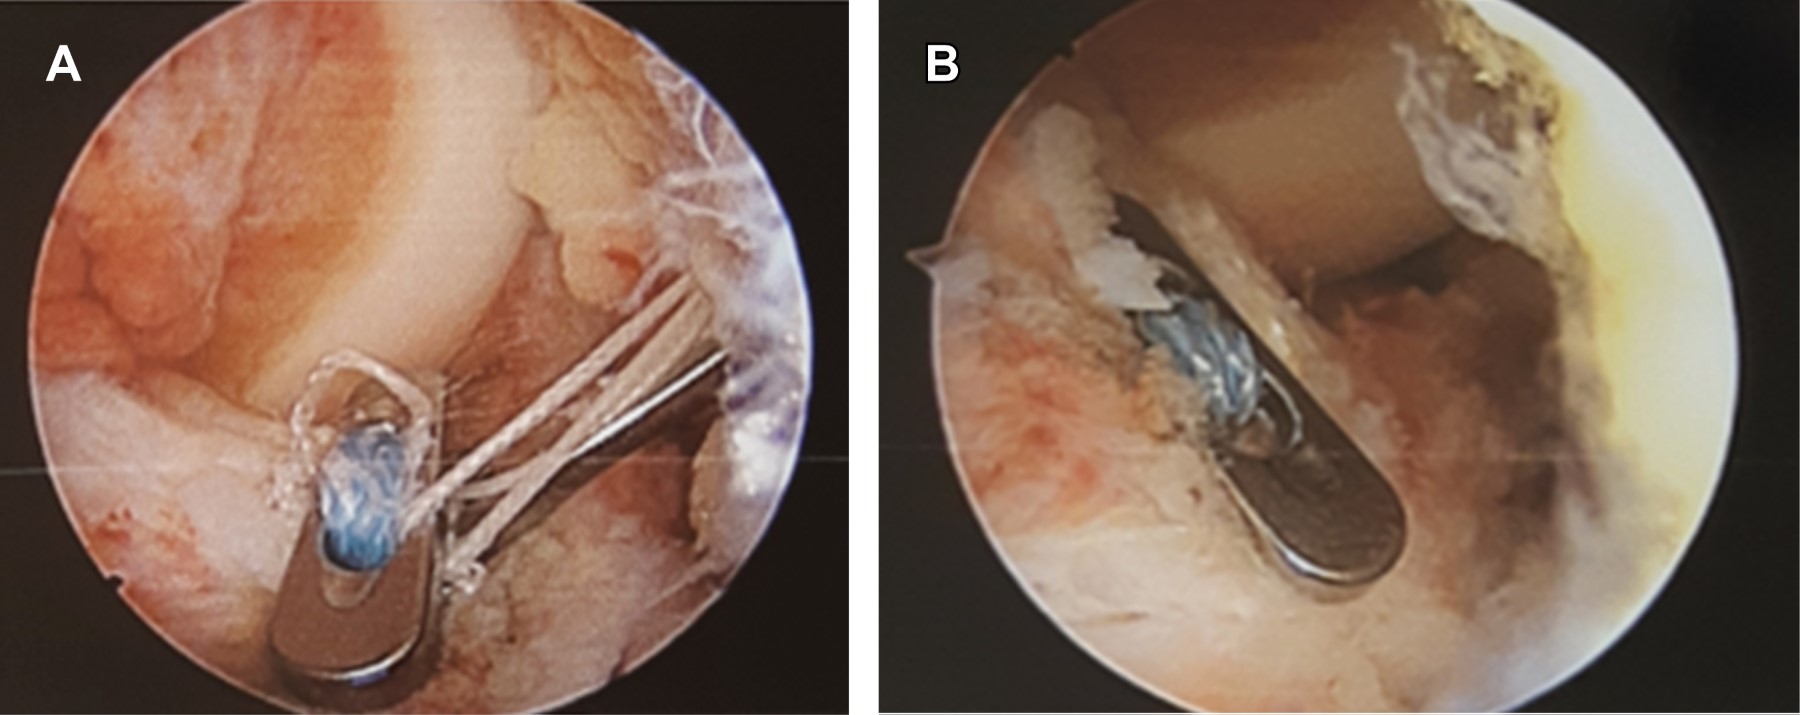

Se programó para reducción de meseta tibial por vía artroscópica mediante sistema TightRope, para lo que se coloca al paciente en decúbito supino, con rodilla a 90o de flexión y sujetador, se realizan portales anteromedial y anterolateral de rodilla derecha, con lo que se vacía hemartrosis de rodilla derecha, limpiando el foco de fractura. Se procede a realizar incisión en tibia proximal en superficie anteromedial para perforar túnel tibial mediante colocación de guía para ligamento cruzado anterior a 55o, se perfora con broca 3.5 mm a través de fragmento de espina tibial reducido con la misma guía, introduciendo desde túnel tibial un FiberStick con sutura de FiberWire para recuperar suturas de TightRope. Se extraen cabos de sutura a través de túnel tibial y se pasa TightRope a través de portal anteromedial, con las suturas atravesando fragmento de espina tibial. Se gira TightRope a su posición horizontal y se tensa con cuidado de no dañar el fragmento de espina tibial (Figuras 3 y 4), se fija en pared anteromedial de tibia proximal con otro TightRope distal circular anudando suturas, y se cortan excesos de éstas. Se cierran portales e incisión de tibia proximal, se cubre con vendaje de Jones y se coloca rodillera mecánica graduada a 0° de extensión. En consultas subsecuentes se fue ampliando el arco de movilidad de rodilla a 45° de flexión y se verificó con control radiográfico la consolidación del foco de fractura. Comienza con apoyo parcial y continúa con fisioterapia en casa cuatro semanas después de la cirugía, ampliando el arco de movimiento a 90o de flexión.

Entre las técnicas descritas se encuentra el uso de clavillos de Kirshner percutáneos, fijación con tornillos guiados por artroscopia, grapas y el uso del sistema TightRope.3,4,6 Muchos de estos procedimientos requieren de una segunda intervención para el retiro de material, además de asociarse a complicaciones como fatiga del implante, aflojamiento o migración, infección y ausencia de consolidación.4,6 Se ha encontrado además en un estudio en cadáveres que la fuerza de fijación con sutura FiberWire es mayor que la de fijación con tornillos.4

Se ha descrito una técnica en la que se atraviesan las fibras distales del ligamento cruzado anterior con FiberWire o Ethibond y con fijación distal con un TightRope de cuatro agujeros contra la cortical de tibial proximal.3 Esta técnica requiere una perforación adicional para la fijación provisional con clavillo de Kirshner. Consideramos que el uso de un botón de TightRope proximal que tracciona el fragmento óseo sin involucrar las fibras del ligamento cruzado anterior, es más bondadoso con los tejidos nativos, además de que no se pasa sutura por los bordes del fragmento, con lo que puede comprometerse el contacto y la congruencia entre el fragmento de la espina tibial y el resto de la epífisis, además de requerir una perforación única de 3.5 mm del fragmento de la espina tibial, por lo que conserva más su integridad. También se han descrito técnicas que requieren de dos orificios a los lados del fragmento a reducir que ofrece una reducción adecuada.7 Sin embargo, preferimos mantener las perforaciones al mínimo para dañar lo menos posible la fisis de crecimiento.

Figura 3

Figura 4